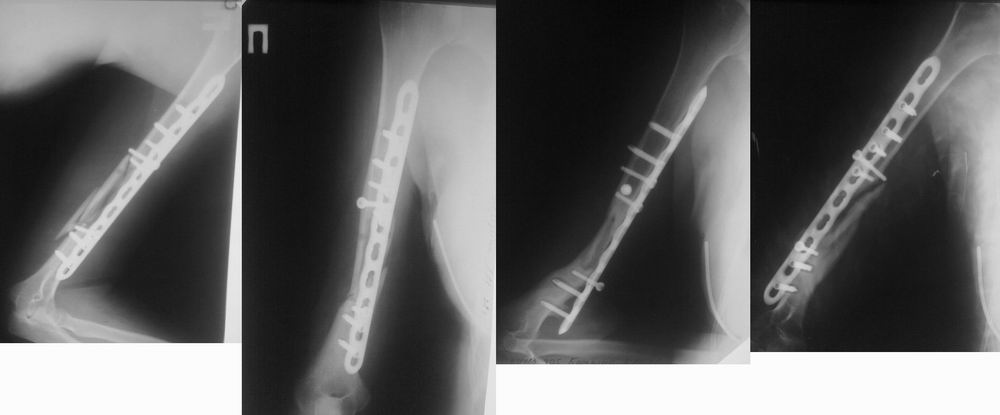

[Ortho] Ложный сустав плечевой кости

Снимки в динамике